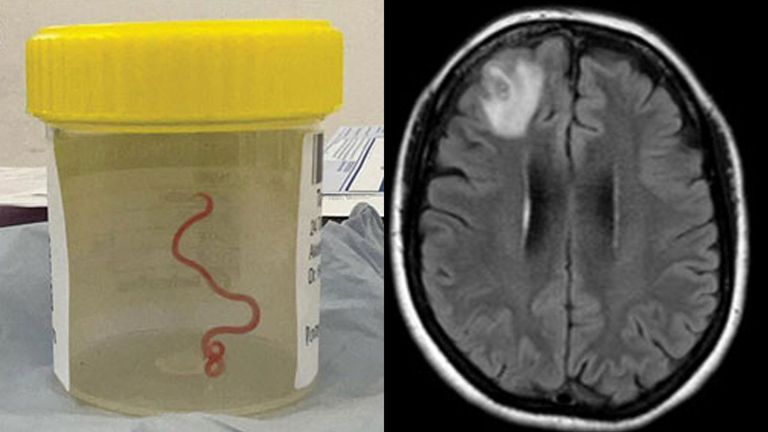

काठमाडौँ : विश्वमै पहिलो पटक एक अस्ट्रेलियाली महिलाको मस्तिष्कमा ८ सेमी (३ इन्च) को जुका जिउँदै भेटिएको वैज्ञानिकहरूले बताएका छन् । बीबीसीमा प्रकाशित समाचार अनुसार गत वर्ष अस्ट्रेलियाको क्यानबेरास्थित एक अस्पतालमा शल्यक्रिया गर्दा बिरामीको क्षतिग्रस्त मस्तिष्कको अगाडिको भाग (फ्रन्टल लोब)बाट धागो जस्तो संरचना निकालिएको थियो। उनको उपचारमा संलग्न चिकित्सकहरूका अनुसार महिलालाई विभिन्न प्रकारका नौला लक्षणहरू देखिएका थिए जुन सामान्यतया देखिन्न । पेट दुख्ने, खोकी लाग्ने र राति पसिना आउने, बिर्सने समस्या र डिप्रेसनमा परिणत हुँदै गएको थियो ।

रातो परजीवी त्यहाँ दुई महिना अघिदेखि रहेको हुनसक्ने अनुमान गरिएको छ । यो केसले जनावरबाट मानिसमा सर्ने रोग र संक्रमणको खतरा बढ्दै गएको पुष्टि हुने अनुसन्धानकर्ताहरूको दाबी छ । क्यानबेरा अस्पतालका संक्रामक रोग विशेषज्ञ सञ्जय सेनानायकेले भने, ‘त्यस शल्यक्रिया कक्षभित्र भएका सबैजना त्यो देखेर चकित परेका थिए । सर्जनले त्यसलाई निकाल्न फोरसेप समाते र त्यसलाई निकाले जुन ८ सेन्टिमिटरको हल्का रातो रंगको जुगा थियो ।’

ती महिलालाई जनवरी २०२१ को अन्त्यमा अस्पतालमा भर्ना गरिएको थियो। पछि गरिएको स्क्यानले मस्तिष्कको दाहिने फ्रन्टल लोबभित्र एउटा असामान्य लिजन पत्ता लागेको थियो । उनको रोगको वास्तविक कारण भने जुन २०२२ मा शल्यक्रियाको क्रममा मात्रै देखियो । ‘ओफिडास्केरिस लार्भा मानिसको मस्तिष्कमा पुगेर विकसित भएको तथ्य पहिले रिपोर्ट गरिएको थिएन,’ नयाँ संक्रामक रोगहरू नामक जर्नलकी लेखिका डा. मेहराव हुसेनले उल्लेख गरेकी छन्, ‘मानवमा तेस्रो चरणको लार्भाको विकास उल्लेखनीय छ, किनकि अघिल्लो प्रयोगात्मक अध्ययनहरूले भेडा, कुकुर र बिरालाहरू जस्ता घरपालुवा जनावरहरूमा लार्भाको विकास देखाएको छैन।’